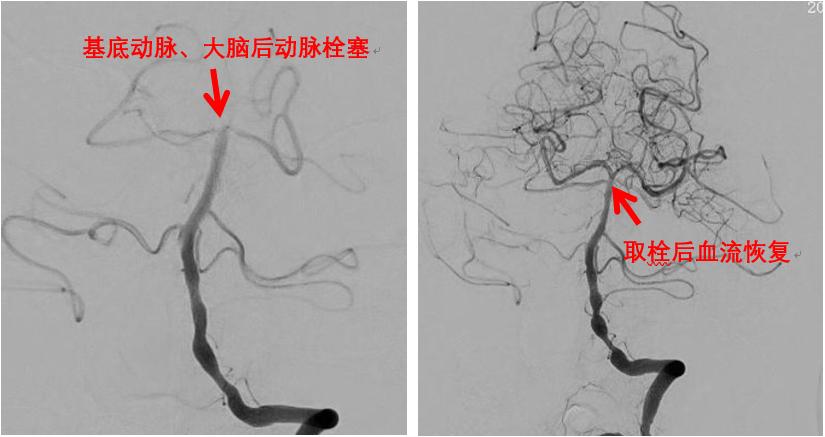

神经血管篇——急性缺血性脑卒中

尤其需要提出的是近年来,介入取栓治疗在急性缺血性脑卒中的治疗中,发挥了极其重要的作用。过去只能依靠药物治疗的脑血栓,如今可以通过介入手术直接从血管内取出血栓,成为一种更为有效的治疗急性缺血性脑卒中的治疗手段。

急性缺血性脑卒中取栓治疗